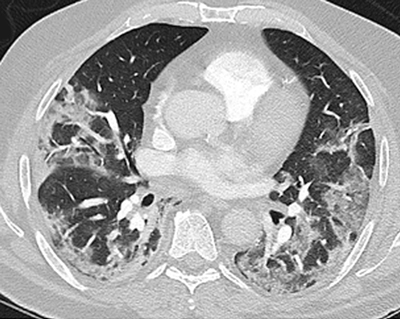

Medicinsk kommentar Mycket ovanligt tillstånd – ökad vaksamhet under pandemin och snabbt multidisciplinärt omhändertagande rekommenderas